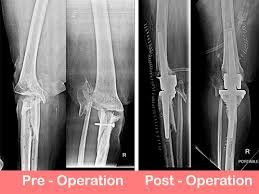

Complex knee replacement, also called revision or specialized knee replacement, involves replacing damaged or failed knee implants or correcting severe deformities and bone loss in the knee joint. This surgery requires advanced techniques, special implants, and expert surgical skills to restore function and stability.

Procedure

The procedure involves:

1. Removing the old or damaged implants

2. Repairing and reconstructing bone loss areas

3. Using special implants such as constrained or hinged prostheses for stability

4. Ensuring correct alignment and function of the knee joint

The surgery is performed under advanced anaesthesia and strict sterile conditions to minimise risks and improve outcomes.